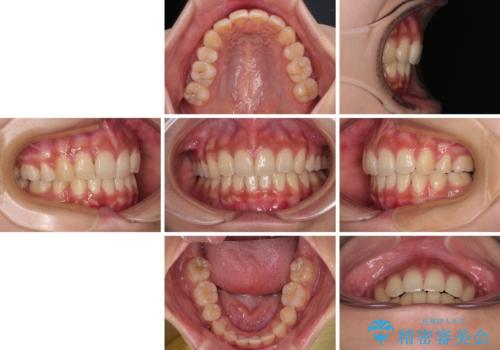

- 前歯の突出感とデコボコを気にして来院された患者様です。

奥歯の噛み合わせをみると、上顎歯列が全体的に前突している状態であり、この咬み合わせのまま歯列を整えると出っ歯になってしまう可能性がありました。

アンカースクリューと補助装置を使用して上顎大臼歯を遠心移動させることで咬み合わせを改善し、更には口元の突出感を改善するために上下左右の小臼歯4本を抜歯し、ワイヤー装置によりデコボコを解消しながら口元の突出感も改善していくこととしました。

上下の前歯が接触する仕上がりとなったので、横顔の印象が大幅に改善されました。